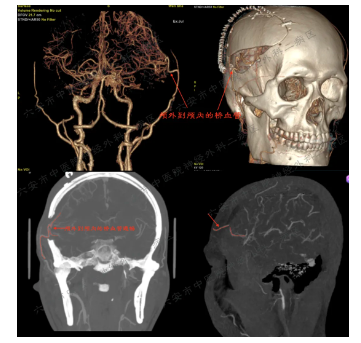

image.png

术后CTA提示:颅外向颅内血管搭桥通畅